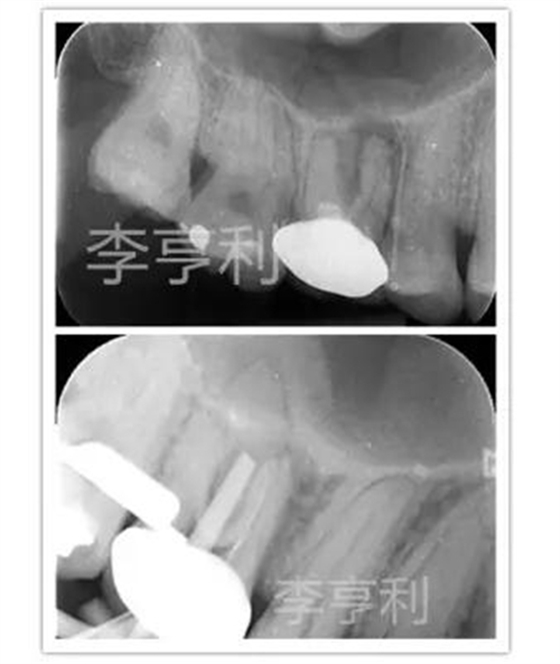

16由于出現(xiàn)瘺管,被轉(zhuǎn)診醫(yī)生診斷為慢性根尖膿腫并開始根管治療。醫(yī)生只能疏通MB到根尖,其它根管均鈣化不通,故轉(zhuǎn)至我處 (圖上)。

當重新打開患牙時,P根和DB的冠1/3已經(jīng)被轉(zhuǎn)診醫(yī)生在探尋根管時大范圍破壞,而且在顯微鏡下仍未能找到根管。隨后告知患者16較差的根管消毒和預后,但患者表示強烈保存患牙的欲望。故決定進行根管治療,但出于對剩余牙體組織的保存,僅預備通暢的MB2和擴大MB的根尖預備,不再嘗試疏通DB和P (圖下)。

術后片顯示除MB根充填能達根尖部,DB和P的根充物都欠充且錐度過大,單純技術要求來看,這是不及格的根管充填 (圖左);

1年回訪發(fā)現(xiàn)16瘺管完全消失,X片也能觀察到明顯的根尖暗影縮小 而且患牙也無任何主觀癥狀,且能正常進行咀嚼,所以從臨床角度來看,這能視為成功的根管治療 (圖右)